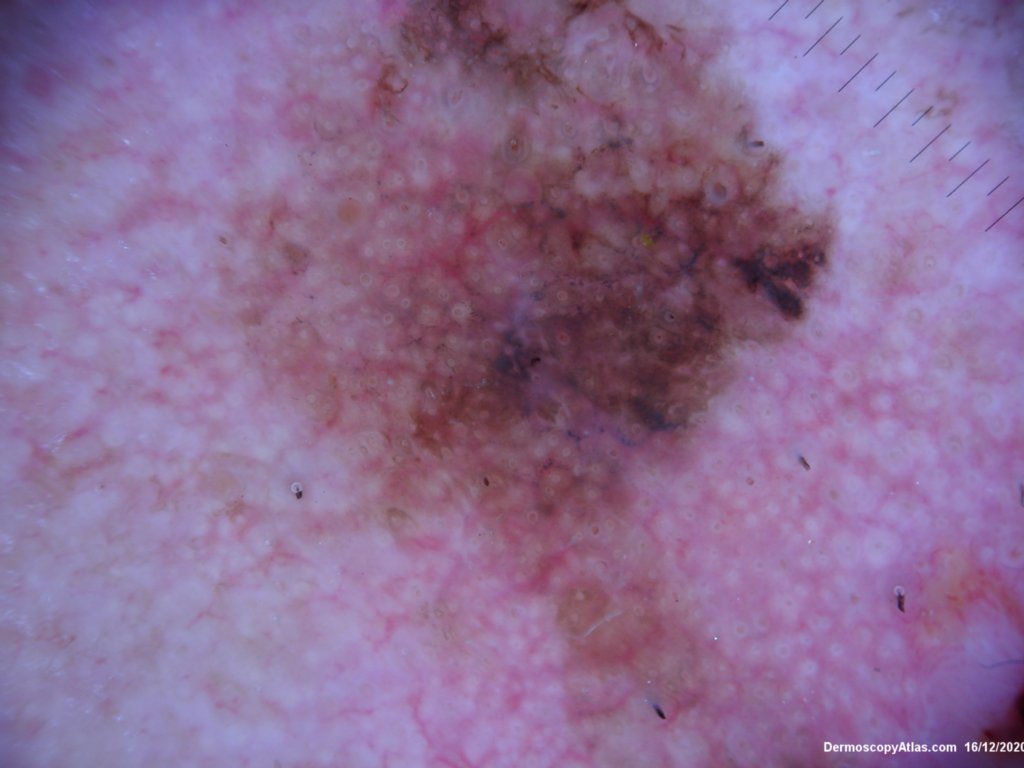

Site: Cheek

Diagnosis: Lentigo Maligna

Description: Pigmented lesion cheek and pink nodule

Elderly male with no past history of melanoma developed these two lesions over a year or so. The lentigo maligna was easy to diagnose on the clinical and dermatoscopy but the nodule was more difficult. Was it an amelanotic melanoma, BCC or SCC were the initial thoughts. Histology showed a well differentiated sebaceous carcinoma. The two lesions were excised in the same specimen with 5 mm margins. Studies failed to show the mutation for the Muir Torre syndrome which can be seen with sebaceous carcinoma.